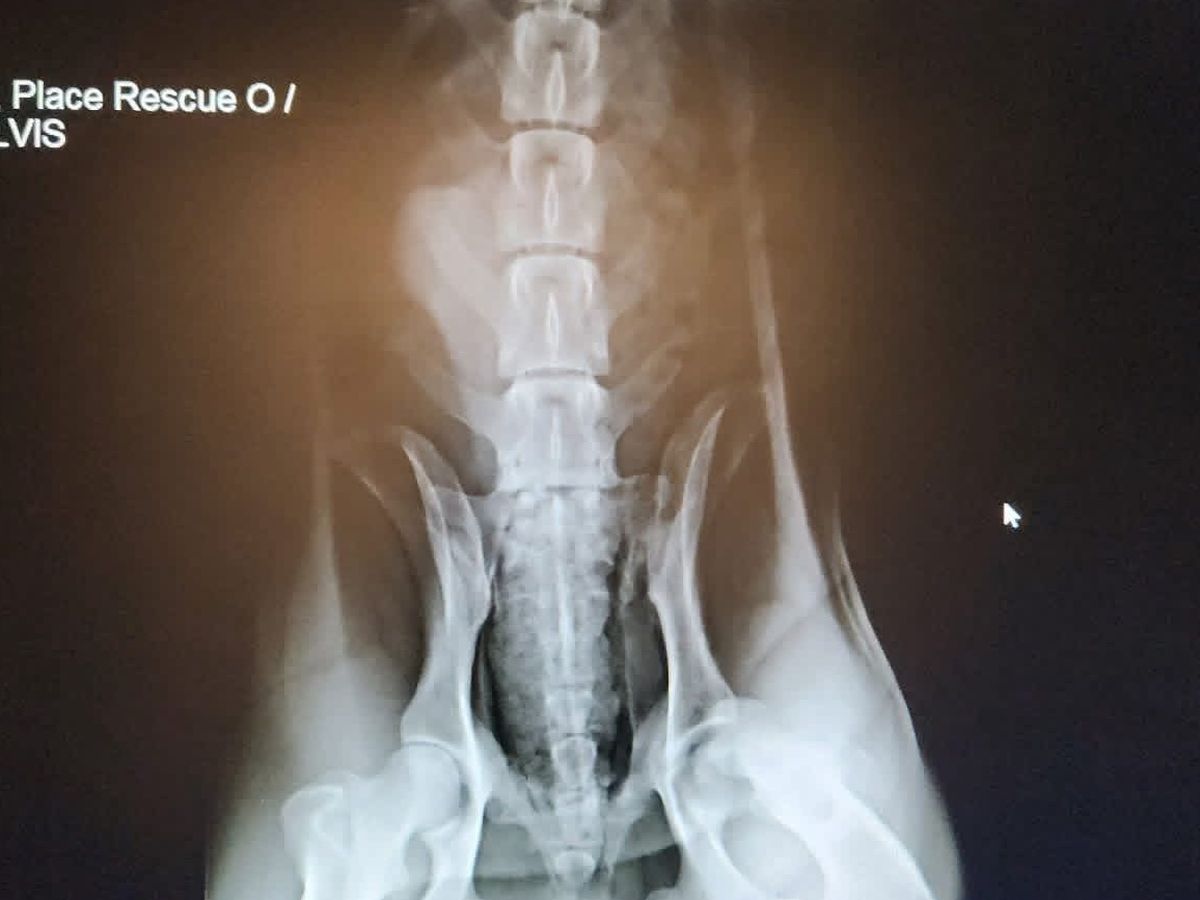

Today is Giving Tuesday, and it’s a day that reminds us why we do what we do. This summer, many of you helped us save Remington after he was hit by a car — and because of the strength of this incredible community, he’s now living his happiest life. Today, we are asking for that same love for Ringo. Ringo was hit by a car, leaving him with severe injuries and in immense pain. His previous caretaker, unable to afford the urgent medical care he needed, was heartbreakingly considering euthanasia. No dog should ever face losing their life simply because treatment is too expensive. We stepped in to make sure Ringo got a fighting second chance. After an emergency assessment with lots of x-rays, it’s clear that Ringo urgently needs a left back leg amputation as well as surgery to repair a broken tibia on the opposite leg. Without these procedures, he cannot walk, rest comfortably, or live anything close to a pain free life. Your support is what makes these miracles possible. Truly we can’t do this without you. If you’re able to give today — or even just share this post — it means the world to us and to Ringo. Please keep him in your prayers and send a little love his way